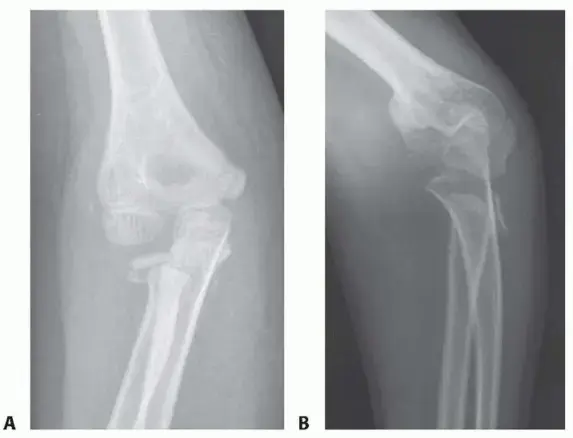

تشخيص الكسر:

عند الاشتباه في كسر رأس أو عنق الكعبرة، سيقوم الطبيب بفحص سريري دقيق للمرفق والذراع، لتقييم مدى الألم، التورم، ونطاق الحركة. بعد ذلك، سيتم طلب الفحوصات التصويرية لتأكيد التشخيص وتحديد نوع الكسر وشدته:

* الأشعة السينية (X-rays): هي الفحص الأول والأكثر شيوعًا، وتوفر صورًا واضحة للعظام لتحديد موقع الكسر ودرجة انزياحه.